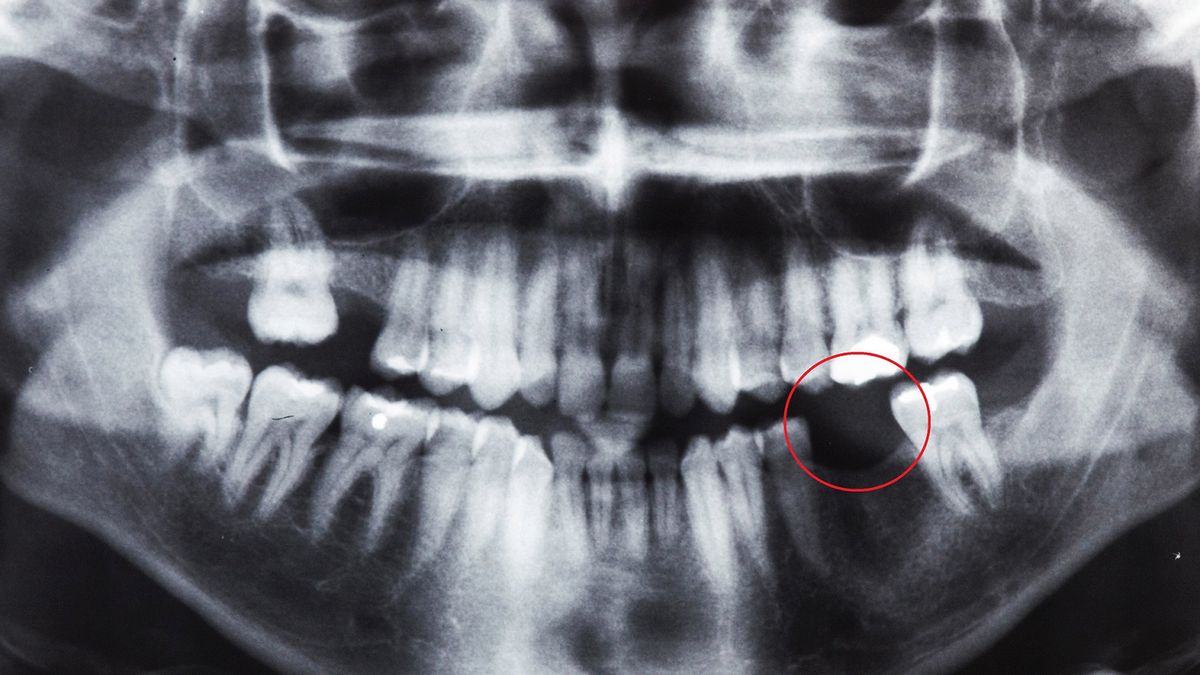

Z badań przeprowadzonych przez naukowców z Uniwersytetu McGill w Kanadzie wynika, że zapalenie przyzębia może mieć silny związek z ciężkim przebiegiem COVID-19 nawet po przyjęciu pierwszej dawki szczepionki. To jedna z częstszych chorób jamy ustnej -dotyka średnio 7 na 10 osób.

Najnowsze analizy wykazały, że osoby cierpiące na zapalenie przyzębia są 3,5 razy bardziej narażone na hospitalizację oraz 8,8 razy bardziej na śmierć w związku z przebyciem COVID-19. Prawdopodobieństwo, że będą wymagały umieszczenia pod respiratorem, wrasta czterokrotnie.

Prowadzący badania lekarz wyjaśnił, że zapalenie przyzębia, będące formą stanu zapalnego, sprawia, że organizm znajduje się w stanie walki z chorobą, przez co osłabiony przystępuje do walki z SARS-CoV-2. To może przyczyniać się do ciężkiego przebiegu COVID-19.

Inne choroby zębów też mogą wpływać na przebieg zakażenia koronawirusem

Naukowcy z Birmingham sugerują, że nie tylko zapalenie przyzębia, lecz także nagromadzenie płytki nazębnej może mieć wpływ na ciężki przebieg COVID-19. Płytka nazębna jest lepką i bezbarwną warstwą bakterii i węglowodanów. Jej nagromadzenie się może prowadzić do próchnicy zębów oraz chorób dziąseł. Periodontopatie (choroby przyzębia) umożliwiają drobnoustrojom chorobotwórczym, przedostanie się do krwi.

"Środowisko jamy ustnej stanowi doskonałą pożywkę dla wirusa. Ślina jest rezerwuarem SARS-CoV-2, dlatego każde naruszenie obrony immunologicznej w jamie ustnej ułatwia przedostawanie się koronawirusa do krwiobiegu przez kieszonkę przyzębia. Z naczyń krwionośnych dziąseł wirus przenika przez żyły szyi i klatki piersiowej aż do serca, a następnie jest pompowany do tętnic płucnych oraz do małych naczyń na obrzeżach płuc" - tłumaczą autorzy badań.